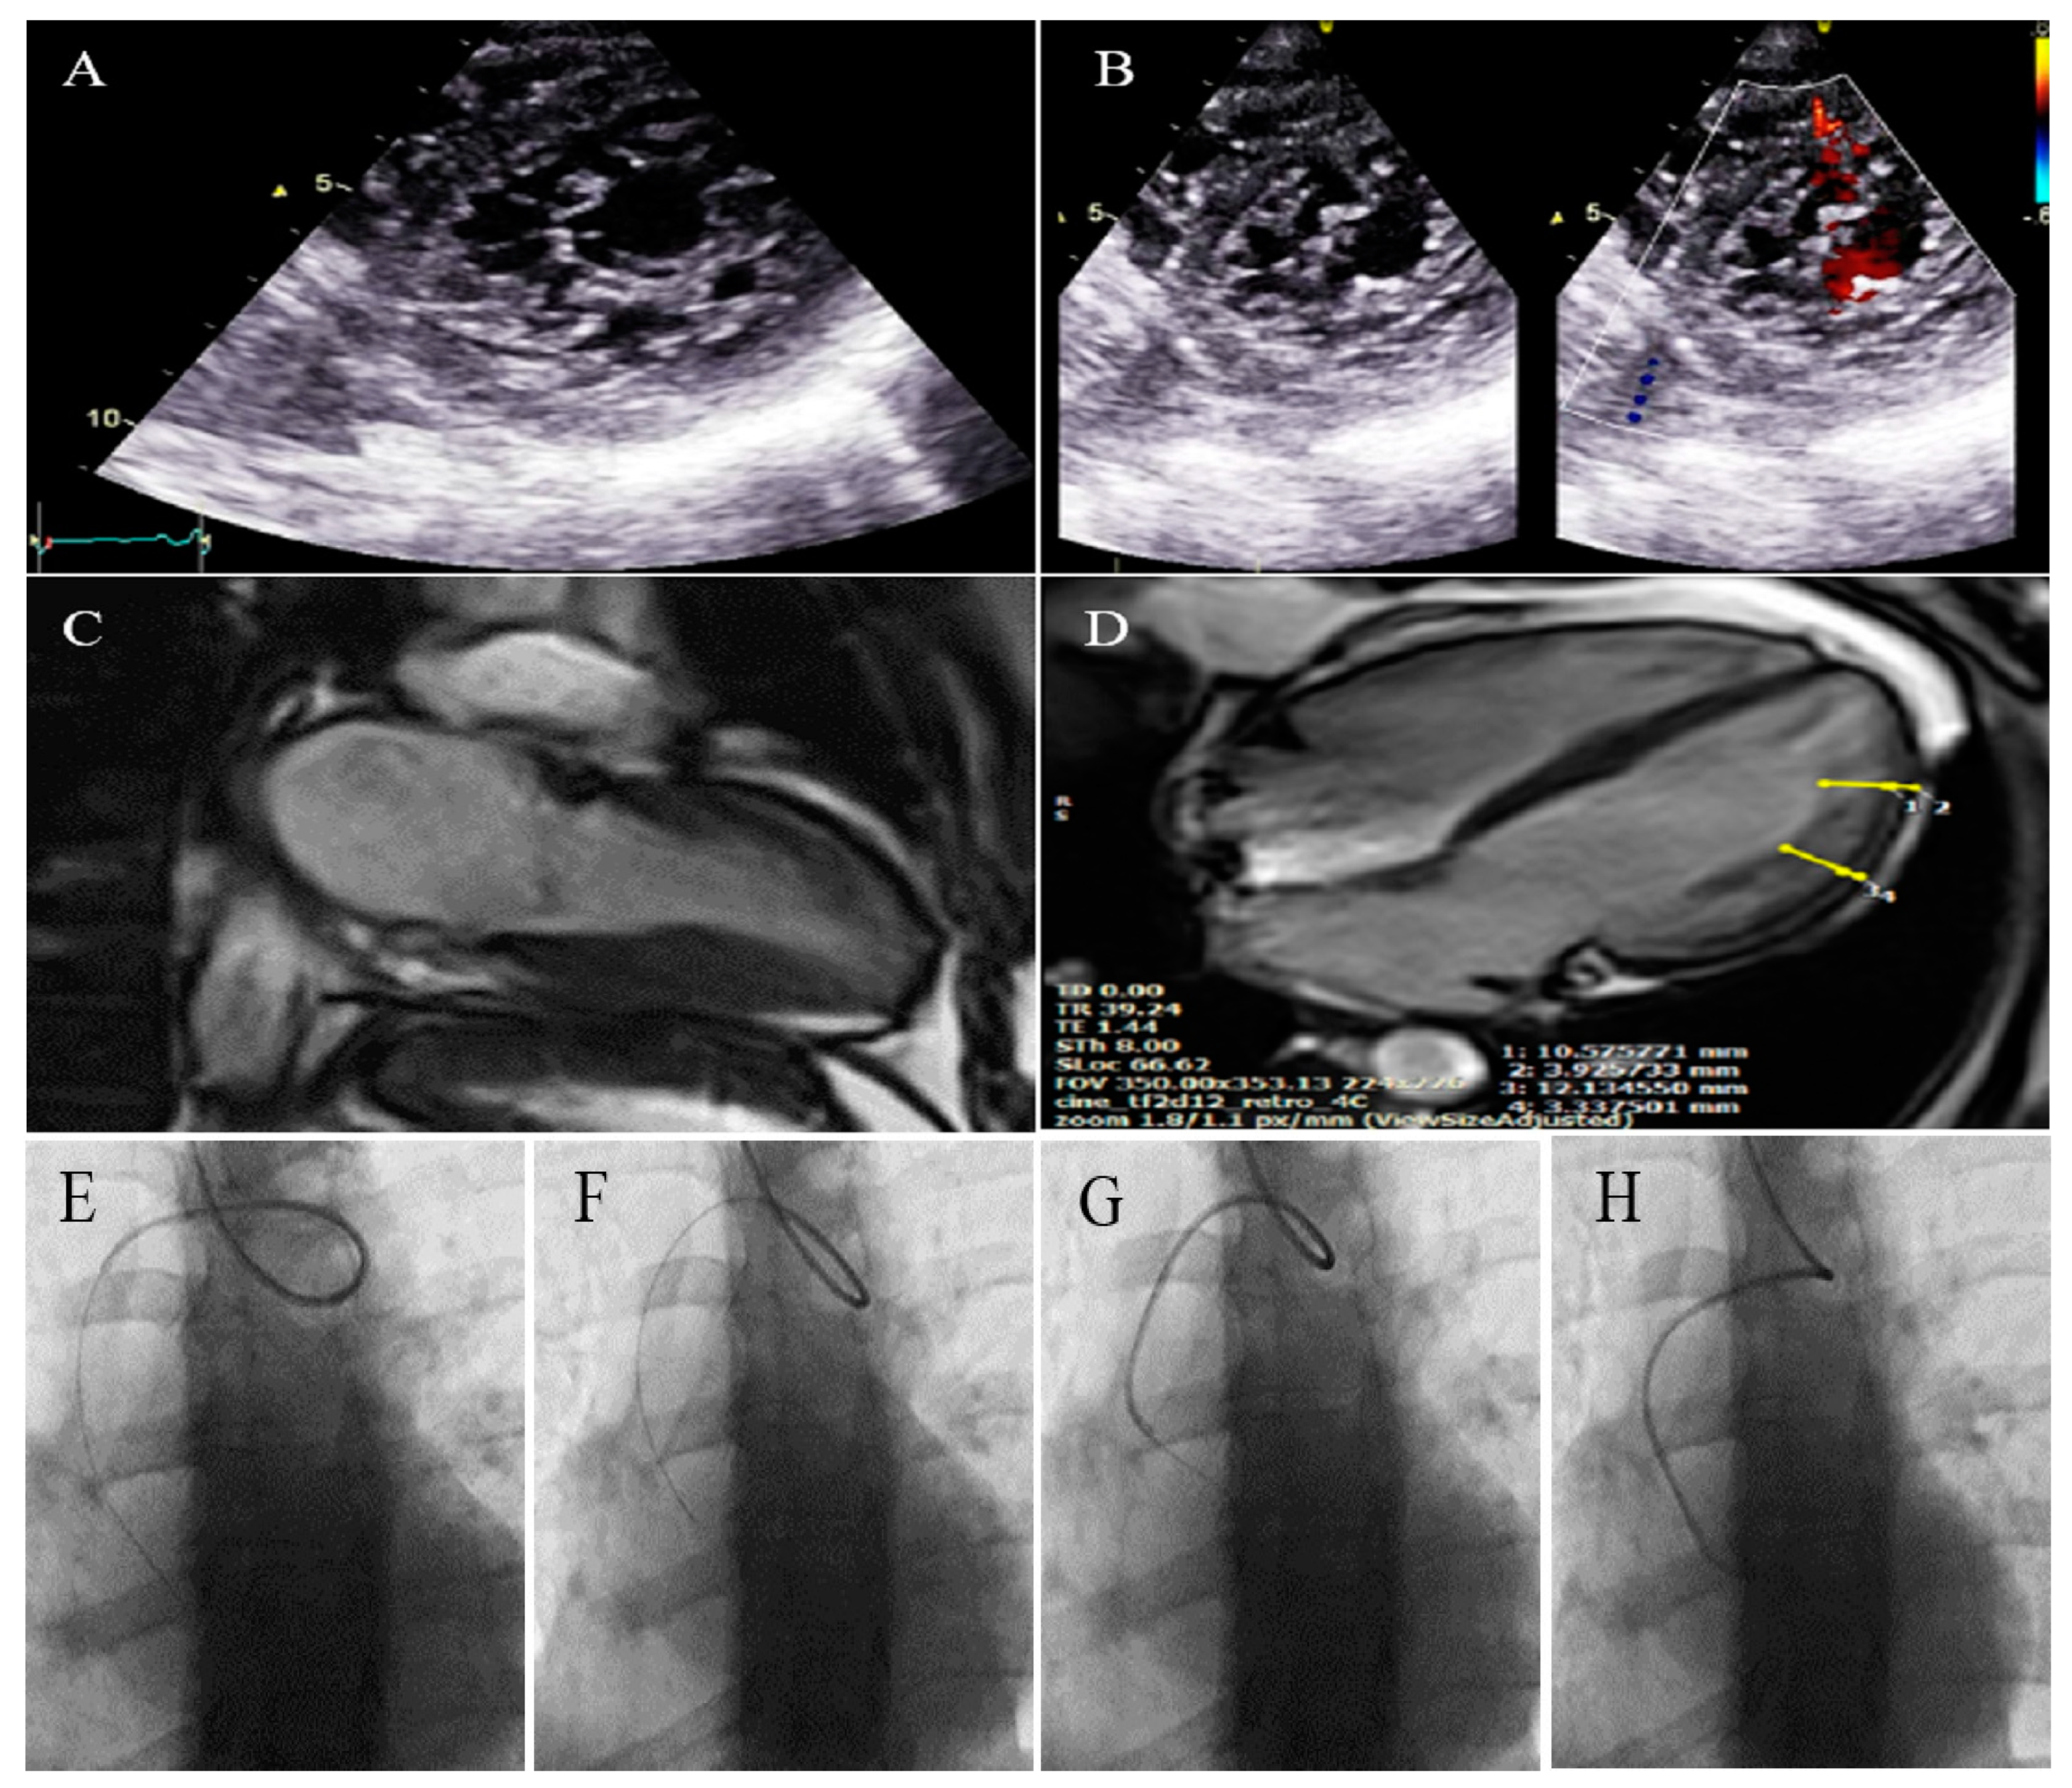

2.12. Case #12. BVNC with a Dilated Aorta

| 12 | M | 58 | History of palpitation and shortness of breath on heavy exercise | − | BVNC, LVEF = 55% | Dilated aorta | − | + | carvedilol; 6.25 mg BID | Doing well |